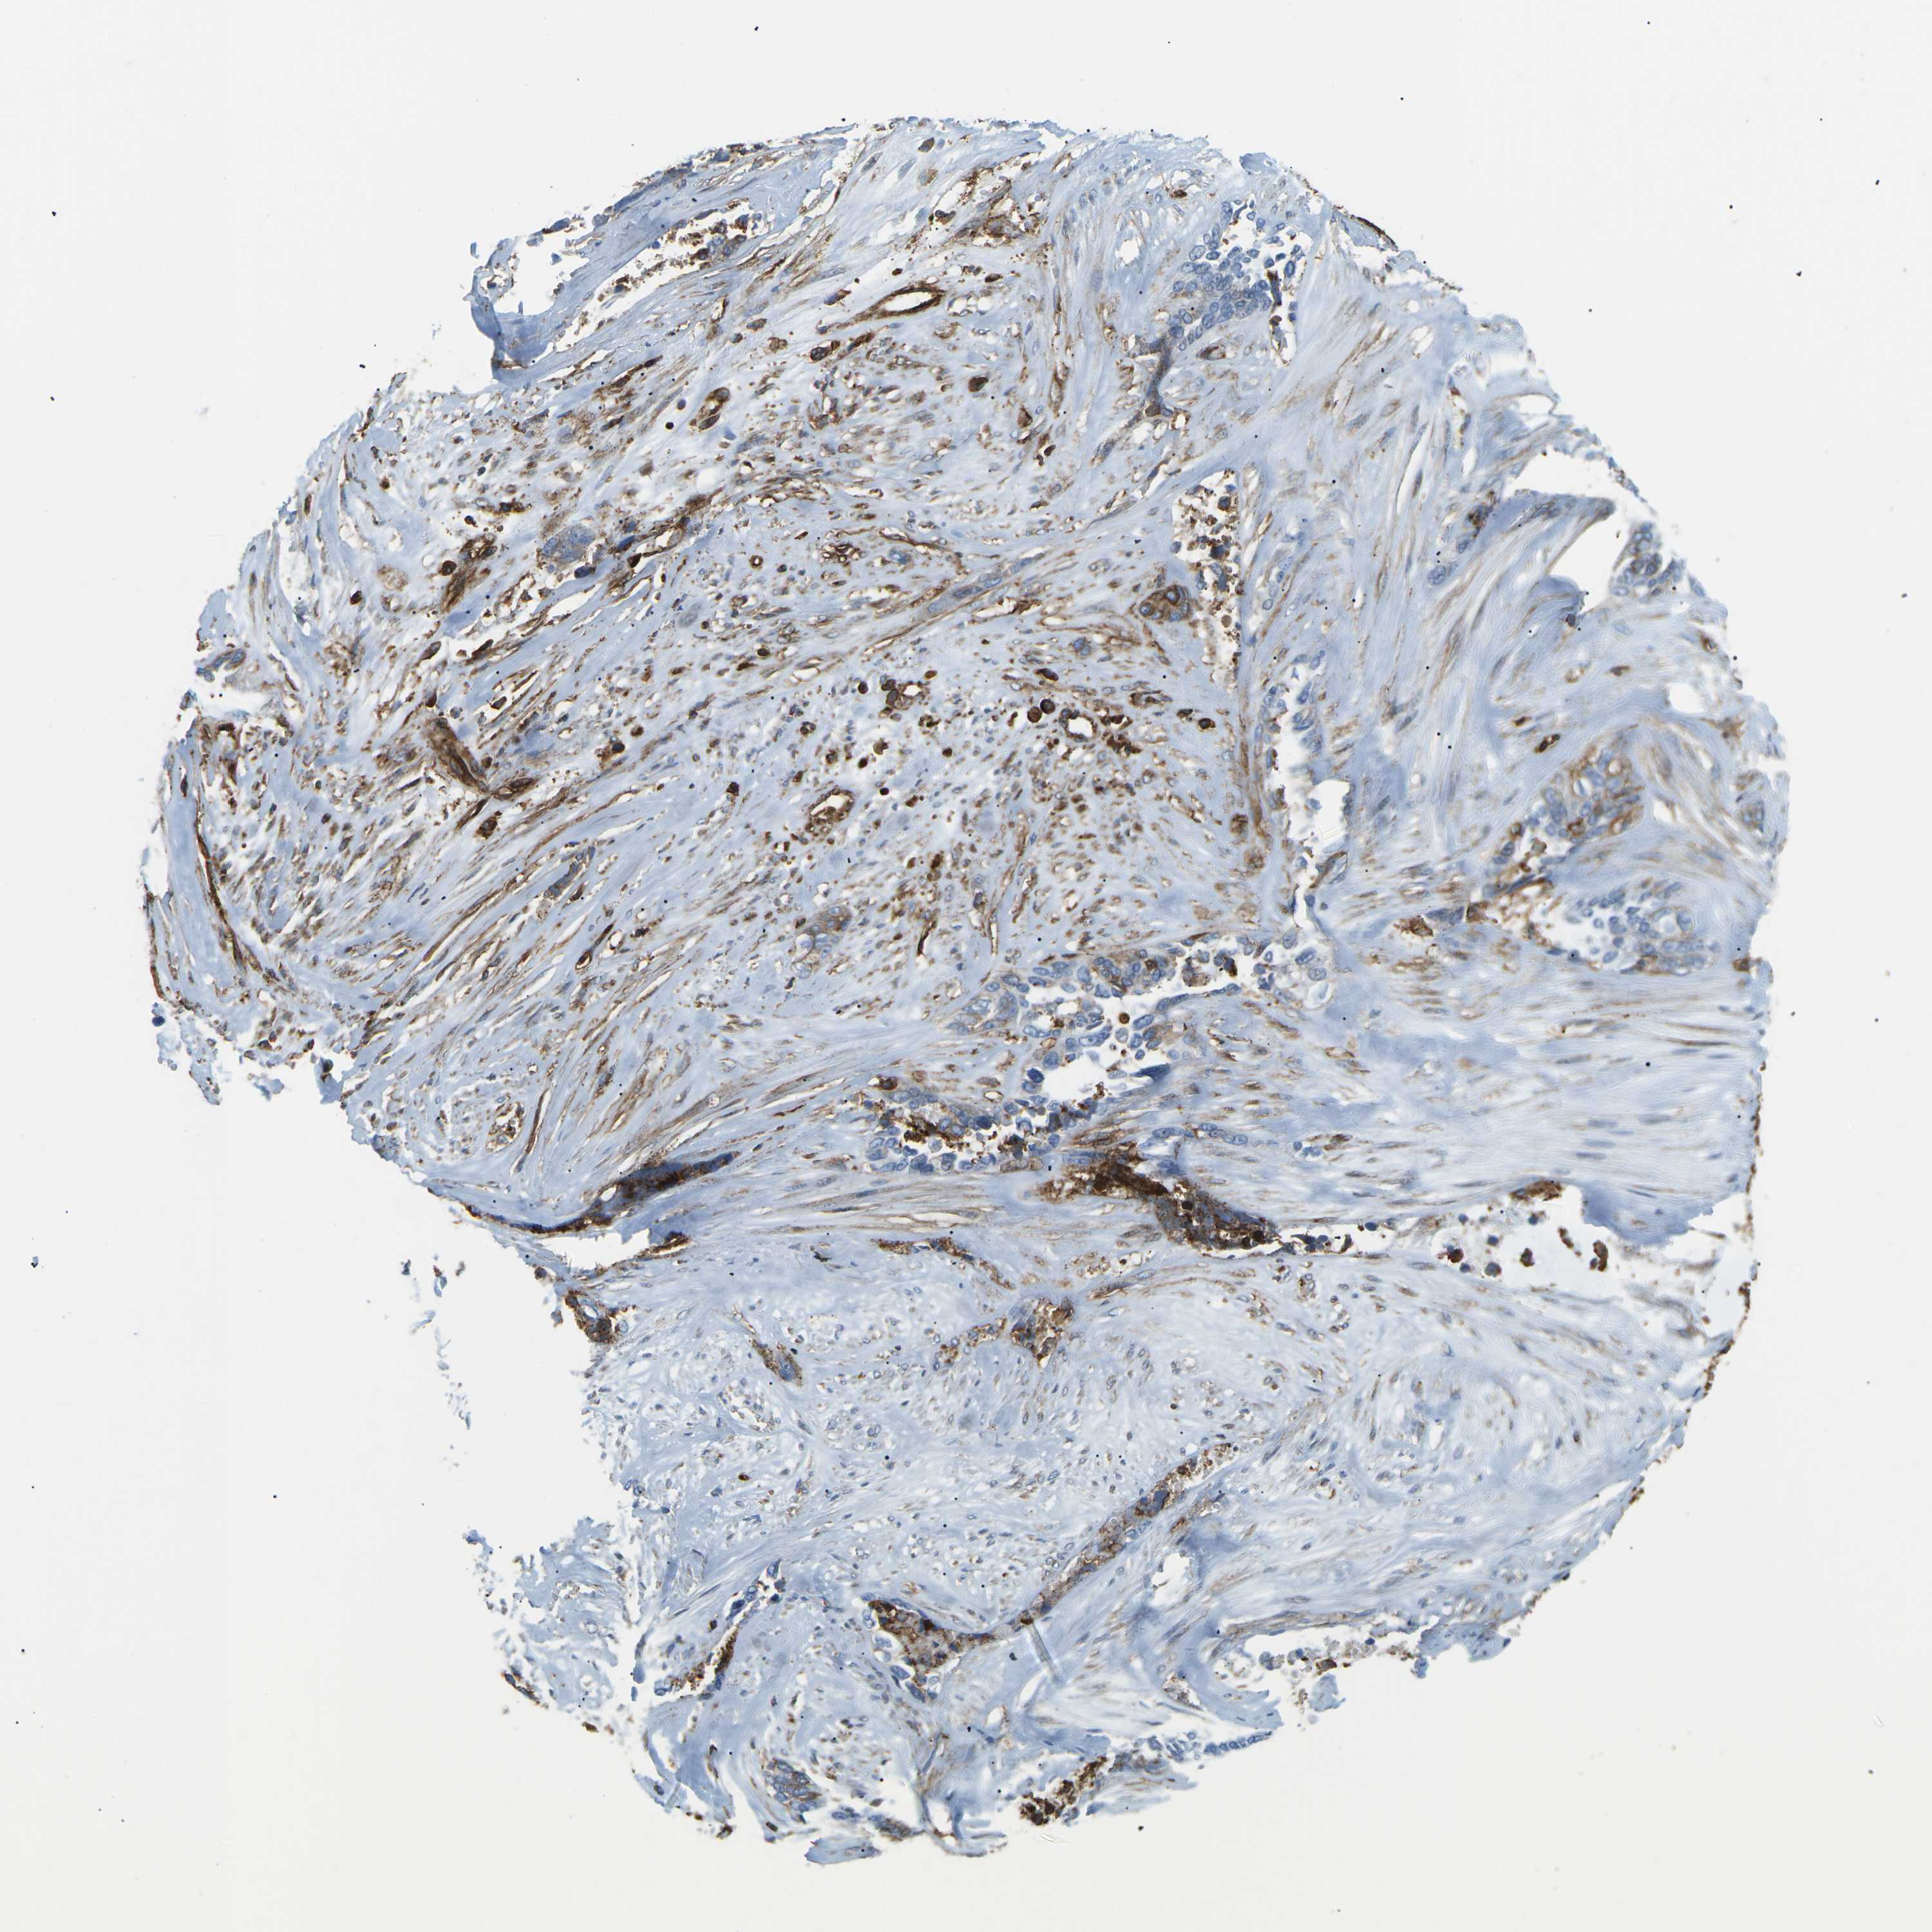

OVARIAN CANCER - Protein expressioni

A mouse-over function shows sample information and annotation data. Click on an image to view it in a full screen mode. Samples can be filtered based on level of antibody staining by selecting one or several of the following categories: high, medium, low and not detected. The assay and annotation is described here.

Note that samples used for immunohistochemistry by the Human Protein Atlas do not correspond to samples in the TCGA dataset.

Antibody stainingi

Antibody staining in the annotated cell types in the current human tissue is reported as not detected, low, medium, or high, based on conventional immunohistochemistry profiling in selected tissues. This score is based on the combination of the staining intensity and fraction of stained cells.

Each image is clickable and will lead to virtual microscopy that enables deeper exploration of all samples and also displays staining intensity scores, fraction scores and subcellular localization as well as patient and tissue information for each sample.

Antibody CAB015418

Staining

High

Medium

Low

Not detected

Intensity

Strong

Moderate

Weak

Negative

Quantity

>75%

75%-25%

<25%

None

Location

Nuclear

Cytoplasmic/membranous

Cytoplasmic/membranous,nuclear

Cystadenocarcinoma, serous, NOS

Carcinoma, endometroid

Cystadenocarcinoma, mucinous, NOS

Carcinoma, NOS